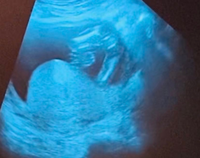

エコー性別について妊娠5ヶ月のエコー写真です 突起物がないので女の子で Yahoo 知恵袋

妊娠5ヶ月 女の子かも- 妊娠16週(妊娠5ヶ月)に入りました!赤ちゃんの成長や性別は? 早くも妊娠6ヶ月(妊娠週)に突入しました! 目次 妊娠6ヶ月 胎動を感じやすくなる; 妊娠 妊娠6ヶ月。しっかりエコーで見えても女の子の判断って難しいですか? 性別を早く知りたい妊娠21週の妊婦です。 5ヶ月、6ヶ月の健診でお股がしっかり見え、何もついていなかった場合は女の子でほぼ 質問No